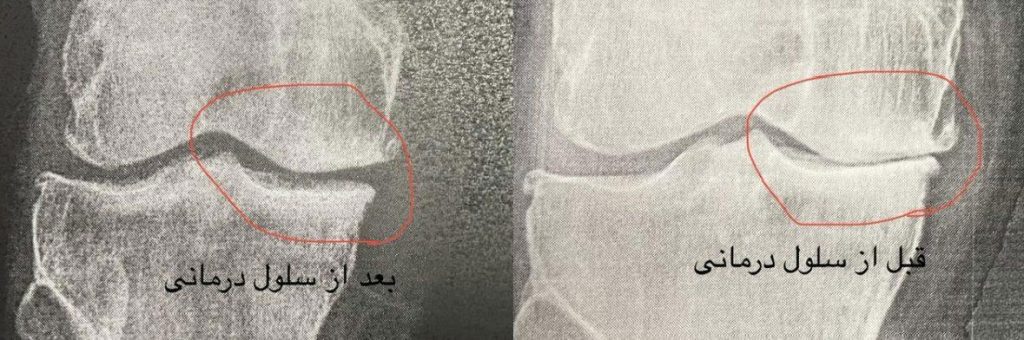

بهترین روش درمان آرتروز زانو با تزریق سلول بنیادی به مفصل زانو

این درمان غیرتهاجمی می باشد و برای مشکلاتی مانند استئوآرتریت، آسیبهای غضروفی و التهابهای مزمن مفصلی کاربرد دارد. مطالعات نشان میدهد که در 80تا 90درصد موارد، بهبود قابل توجهی در عملکرد مفصل مشاهده میشود،پزشکان و متخصصین این روش را به عنوان جایگزینی مناسب برای جراحیهای سنتی در نظر میگیرند.

براساس آخرین پژوهشهای انجمن ارتوپدی آمریکا (AAOS 2023)، سلول درمانی زانو با نرخ موفقیت ۸۹% در آسیبهای درجه ۲، مؤثرترین روش غیرجراحی شناخته شده است